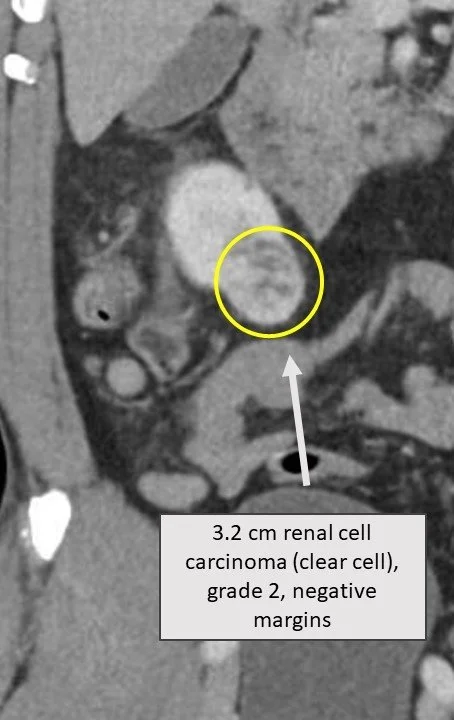

Single port robotic surgery can be employed to remove kidney tumors. In this patient, I removed a 3.2 cm right-sided kidney tumor (image to the right) with “low anterior access” - a 3.5 cm incision above the hip (image to the left). This surgery not only results in one very small scar, but is “retroperitoneal”, meaning it avoids entry into the abdominal (peritoneal) cavity. This can help avoid complications in the abdomen, and delays in post-operative bowel function. It is also a great approach for patients with multiple prior abdominal surgeries, where there may be an excess of scar tissue.